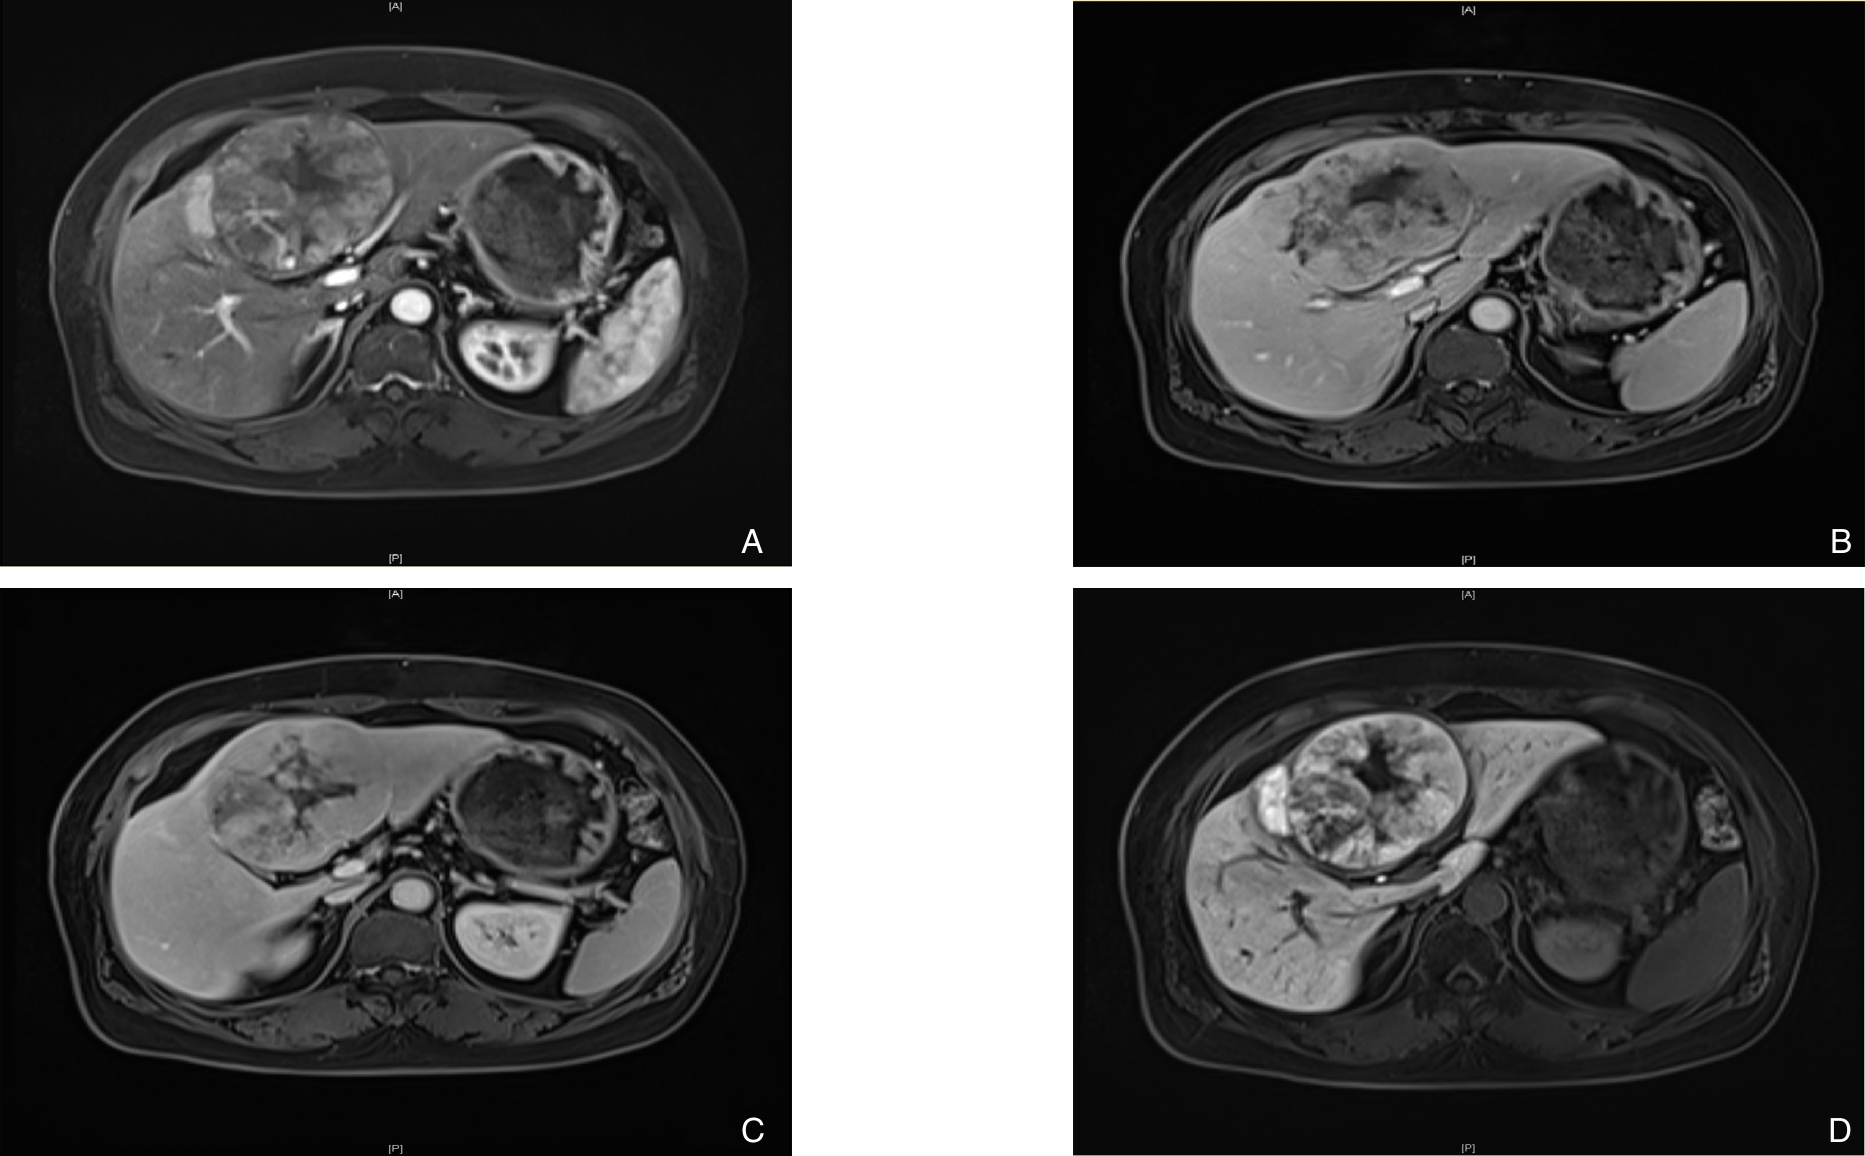

• Clinical application of three-dimensional visualization technology in assessing the spatial configuration of major hepatic vessels and liver lobar volume distribution

2026, 35(1):124-140. DOI: 10.7659/j.issn.1005-6947.250635

Abstract (93) HTML (137) PDF 3.82 M (171) Comment (0) Favorites

Abstract:Background and Aims The hepatic vascular and biliary systems exhibit substantial anatomical variability and complex spatial relationships, posing challenges for precise surgical planning based on conventional two-dimensional imaging. This study aimed to evaluate the clinical value of three-dimensional visualization in characterizing the spatial architecture of hepatic vasculature and bile ducts and to explore its association with hepatic volumetric distribution.Methods A total of 610 living liver donors and 158 patients with bile duct dilatation were retrospectively analyzed. Three-dimensional models of the hepatic artery, portal vein, hepatic veins, and bile ducts were reconstructed from contrast-enhanced CT images. Vascular and biliary anatomical patterns, spatial relationships, and their correlations with hepatic lobe and segmental volumes were systematically assessed.Results Three-dimensional visualization enabled intuitive and comprehensive depiction of hepatic vascular and biliary anatomy. Distinct portal vein configurations were associated with significant differences in regional liver volume distribution, with an increased proportion of the right posterior lobe observed in patients with specific portal vein branching patterns. The presence of an inferior right hepatic vein with a diameter ≥5 mm was also associated with a larger right posterior lobe volume. Analyses of extrahepatic and intrahepatic spatial relationships revealed relatively consistent positional patterns between the right hepatic artery, portal vein, and bile ducts, and a significant correlation was observed between the spatial courses of the right hepatic artery and the right posterior bile duct.Conclusion Three-dimensional visualization provides accurate preoperative assessment of hepatic vascular and biliary anatomy and clarifies complex spatial relationships and their volumetric implications. This technique offers critical anatomical support for precision hepatobiliary surgery and liver transplantation.